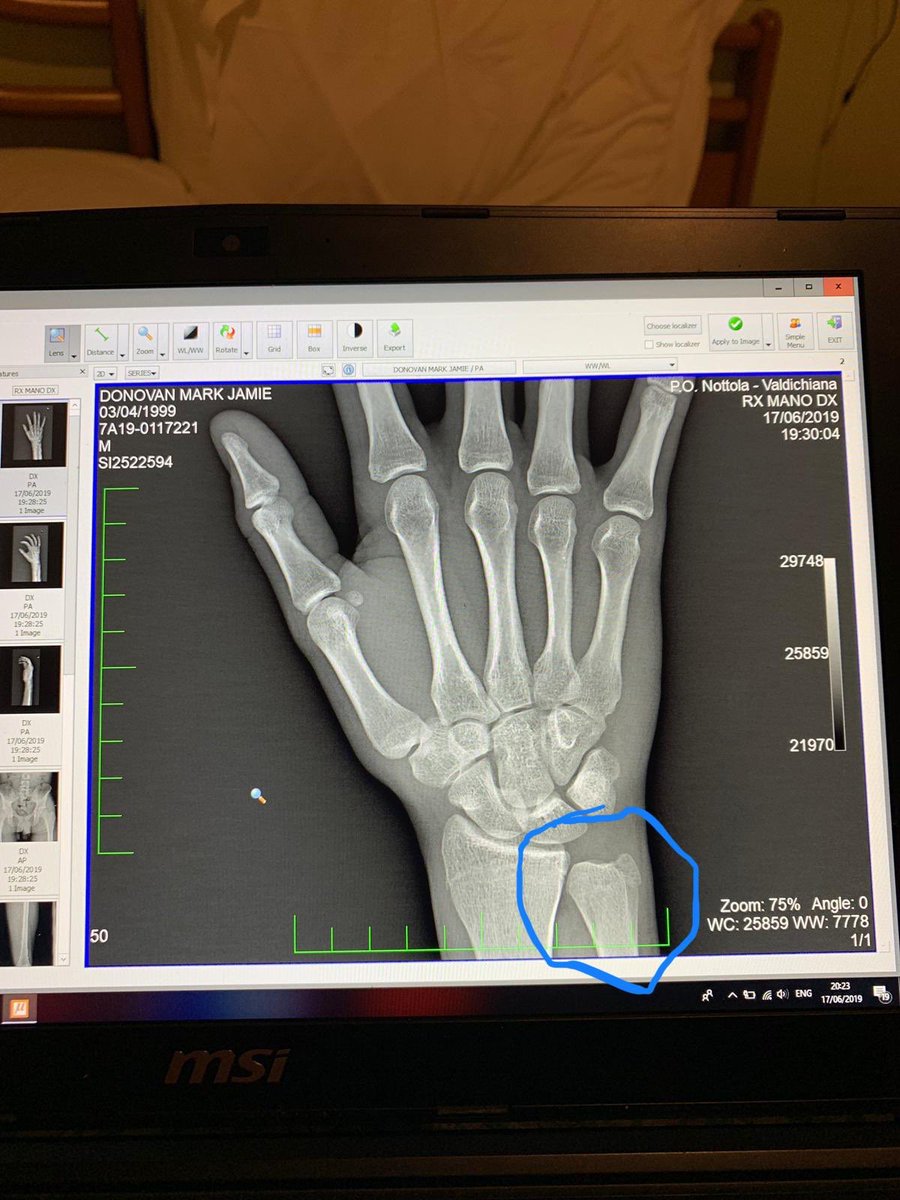

La radiografía que reveló la fractura en su muñeca:

El Giro de Italia Sub 23 despedirá a uno de los grandes favoritos al título, Mark Donovan (Team Wiggins Le Col). El británico sufrió una dura caída, que le provocó una fractura en su muñeca, y no tomará la salida en la quinta etapa.

“Bueno, mi Giro está terminado. Muñeca rota y un hematoma en la pierna izquierda. No puedo tomar un descanso esta temporada después de tener neumonía en abril”, expresó Donovan, quien espera volver para el final de la temporada.